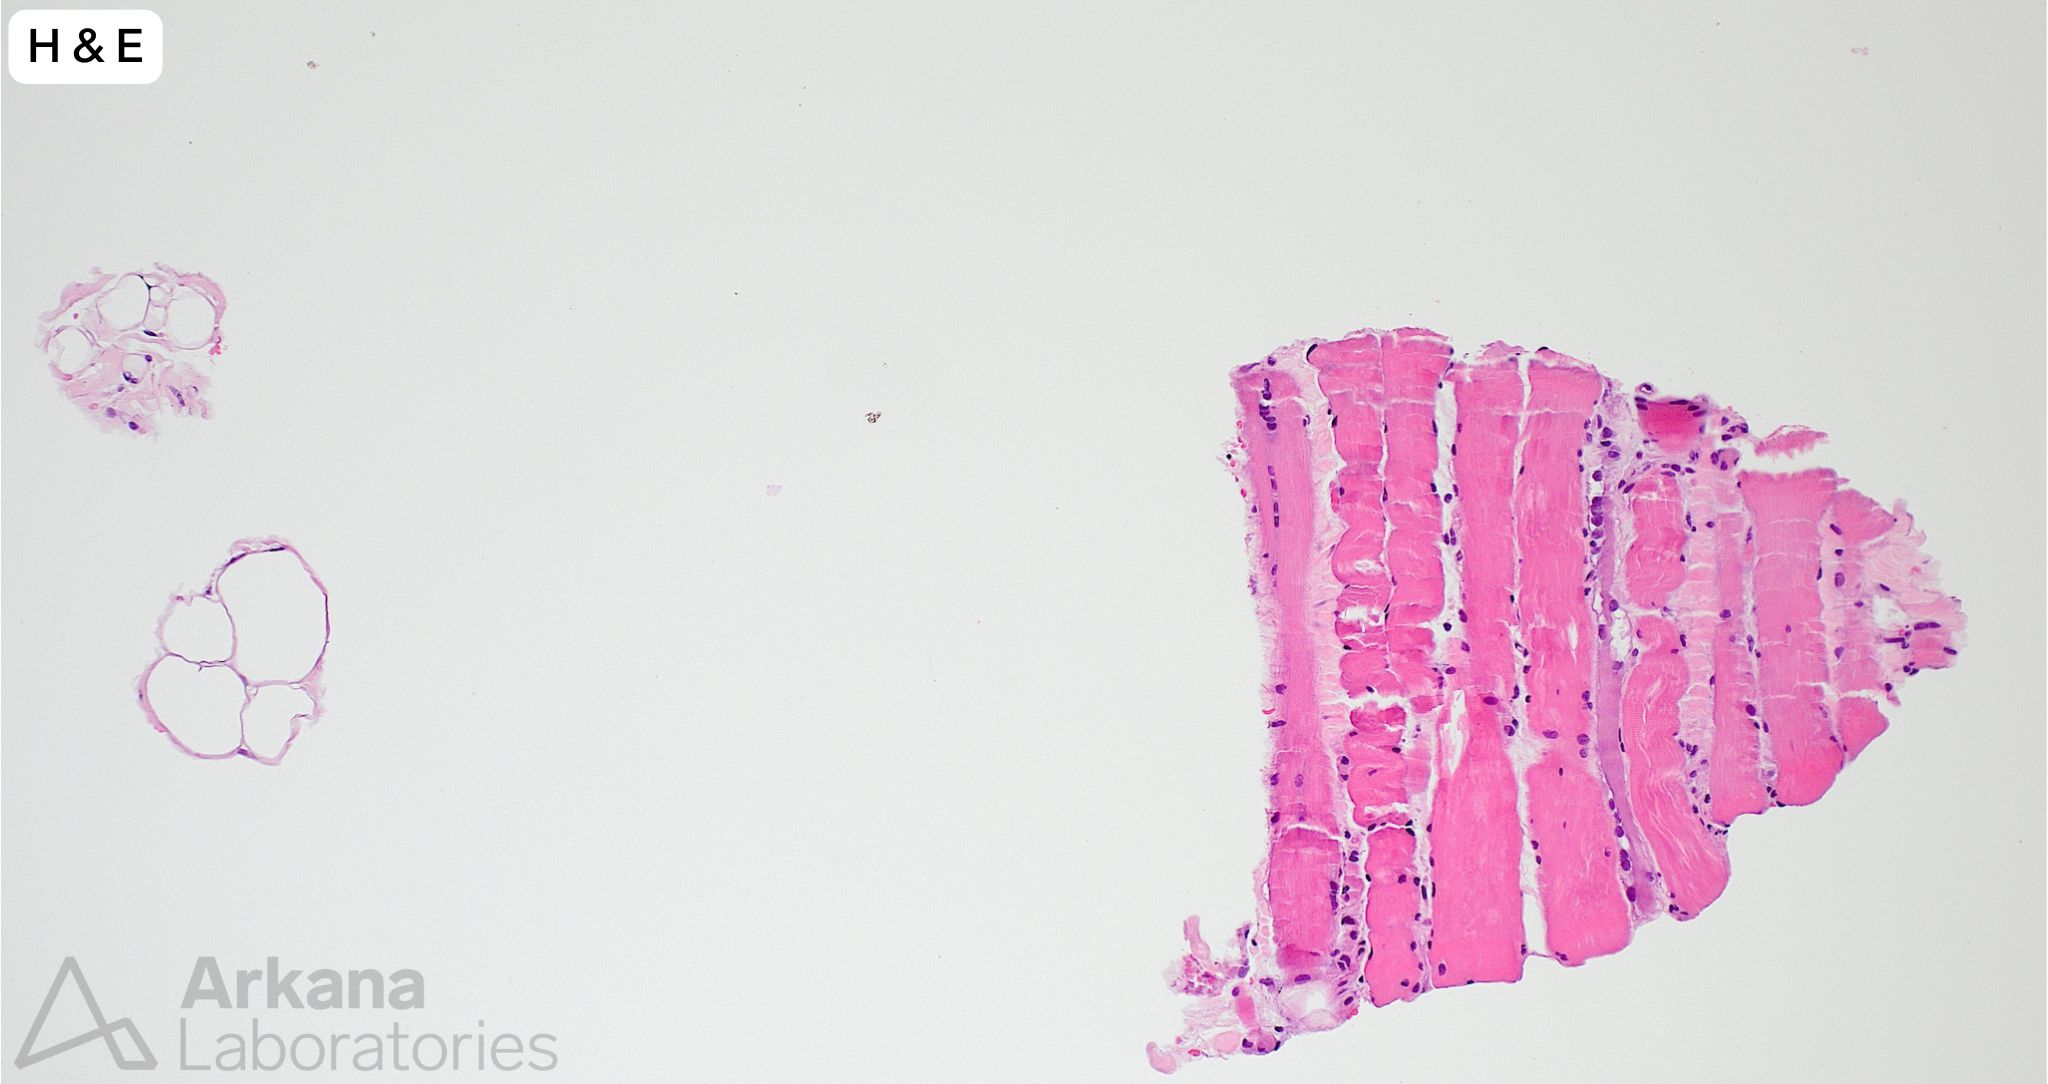

A needle core biopsy was performed of the left thigh. A minute fragment of fibrous tissue was present in tissue available for frozen section. The provided images (low and high magnification) show the total tissue available for evaluation in the formalin-fixed paraffin embedded tissue. The tiny fragment of glutaraldehyde-fixed tissue available for toluidine blue stained sections (image not provided) showed features similar to those seen in the FFPE tissue sections, and a few necrotic myofibers.

- While significant information may be obtained from needle core biopsy samples, the “risk” of an issue of sampling compared to open biopsy is accentuated (i.e. processes involving muscle are frequently patchy in nature and morphologic features to enable a definitive pathologic diagnosis may be only partially represented or not present at all in the tissue submitted for evaluation).

- The number of needle core (16 gauge) biopsies of muscle we receive for evaluation is increasing. While significant information may obtained from such samples, their limitations must be understood. Needle core biopsy of a patient with suspected metabolic myopathy would be inappropriate.